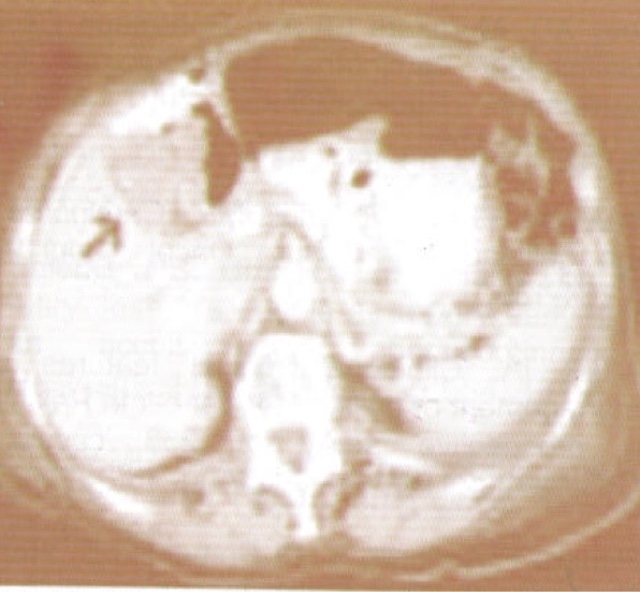

Later CT scan abdomen was done Fig 3 which revealed gallbladder mass .Patient had an inoperable carcinoma of gall bladder and she later developed progressive cholestasis and deep Jaundice and succumbed to her illness unfortunately .

| Fig 3 CT abdomen showing carcinoma Gallbladder (arrow ) |